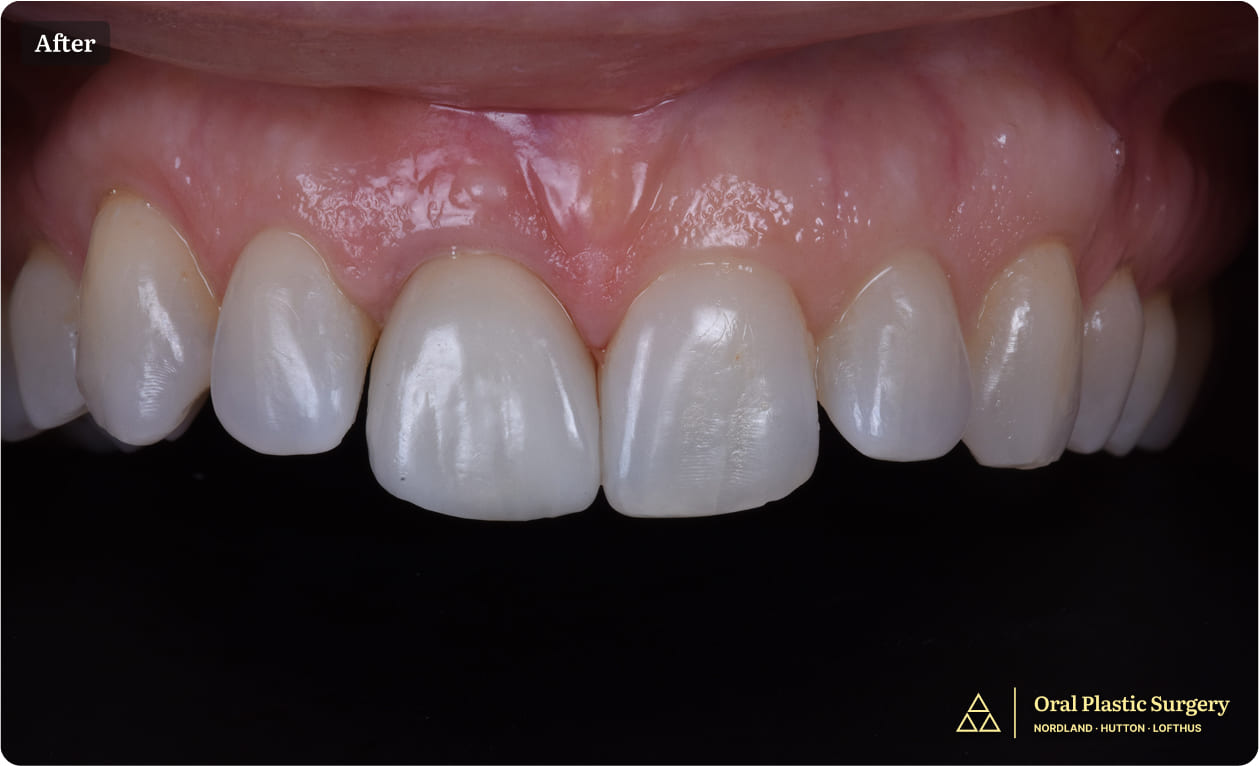

Final implant restoration demonstrating natural emergence profile, ideal tissue architecture, and symmetric integration with adjacent dentition. The result is indistinguishable from a natural tooth.